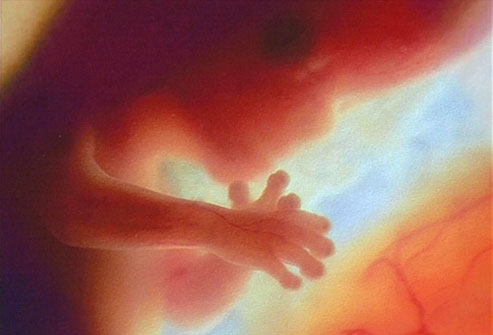

Fetus at 4 Weeks

Fetus at 8 Weeks

Fetus at 12 Weeks

Fetus at 16 Weeks

Fetus at 20 Weeks

Fetus at 24 Weeks

Fetus at 28 Weeks

Fetus at Week 36

All pictures came from:  http://www.webmd.com/baby/slideshow-fetal-development